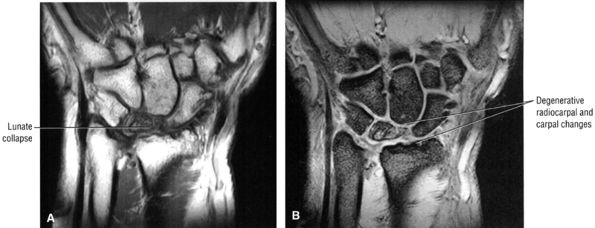

-

Pain and numbness or tingling in the median nerve distribution with increased nocturnal pain and/or burning (can be classified as mild, moderate, or severe based on electrodiagnostic data or by severity of clinical symptoms)

Involvement of the thumb, index, middle fingers, and radial half of the ring finger is most common.

Sensory findings ranging from minimal hypesthesia to complete anesthesia

Muscle atrophy and loss of function are usually late findings, although abductor pollicis brevis involvement and opponens weakness may be seen earlier (opponens atrophy is a late finding).

Positive clinical tests for nerve entrapment: